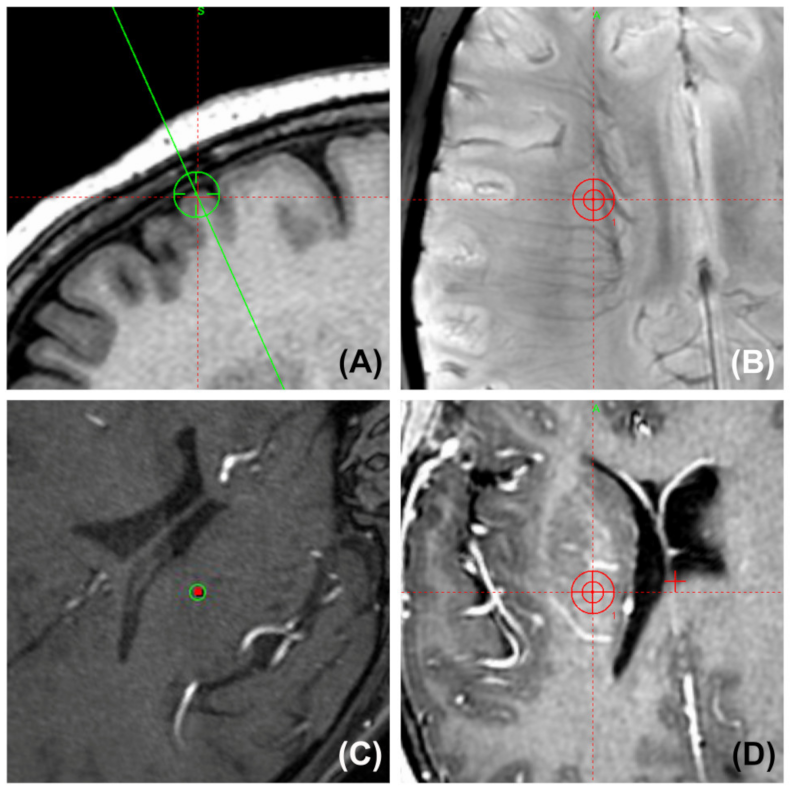

Figure 1.

Axial computed tomography (CT) slices at the hemorrhage sites taken after the health of a 53-year-old man with PD in the non-trajectory planning group deteriorated on the 6th postoperative day. He had suffered from a headache for a few days before falling into a coma. His hematomas were along the trajectory of the definitive electrode in the right frontal lobe (A), basal ganglia, and midbrain (B).

Surgical planning snapshot images show the position of the planned trajectory and its surrounding vessels (two-dimensional probe’s-eye trajectory visualization by SWI, TOF MRA, and T1W-Gd). (A) The entry point is always placed anterior to the coronal suture to avoid injuring the motor region. (B) Preventing the guide tube from puncturing small and deep vessels in the corona radiata by SWI. (C) Confirming that the trajectory was kept far from the arteries in the lateral fissure by TOF MRA. (D) Gadolinium-enhanced MRI shows that the trajectory was kept at a distance from the surrounding arteries and veins in the basal ganglia area.